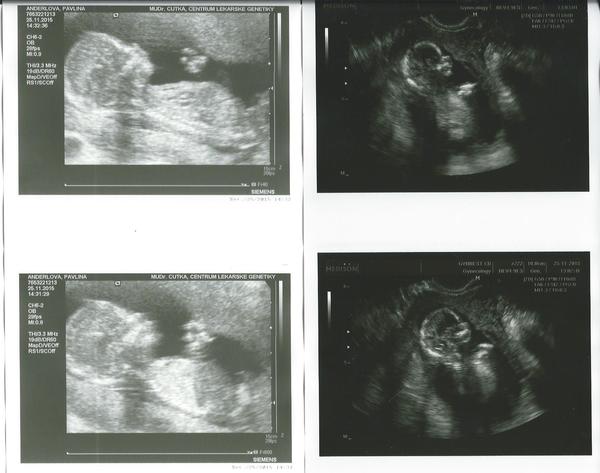

@pavlina1976 Gratuluji... já ti hned říkala, že s těmi jmény bych ještě nezačínala 😀... U nás taky vše OK, mimi sebou šije jak malý čertík. Mě tedy pan doktor Kučera ještě neřekl, co to bude, ale ve 12. týdnu je asi ještě brzy. Třeba se to dozvím na triple test screeningu, který bychom mohli zvládnout ještě do Vánoc, protože na krev k triple testu jdu 17.12. ...

@lenik33 Ten 12tt je ještě brzo....Ale další utz už by to mohlo být vidět 😉 . Já jdu taky příští týden na druhou krev a 10.12. ještě na genetický utz. Tak doufám, že potvrdí, že je vše OK! Věřím, že ano 😀 . A co ty? Mě už naštěstí není tolik špatně, už se cítím lépe 😉